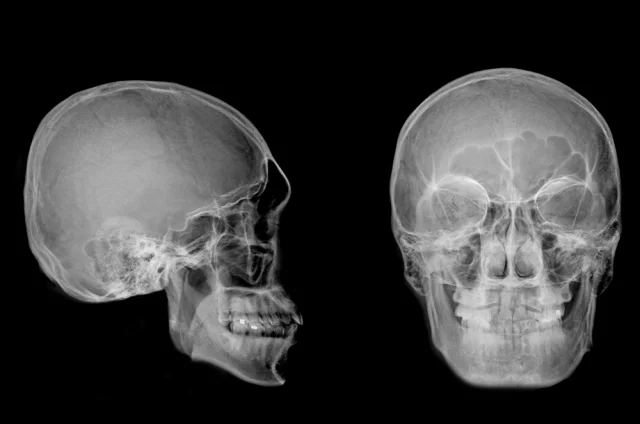

Компьютерную томографию провели в Лаборатории ядерной и инновационной медицины физического факультета Новосибирского государственного университета. Томограф позволил виртуально «удалить» эти покровы и создать точную цифровую, а затем и физическую 3D-модель черепа.

Так удалось узнать, что женщина при жизни получила серьёзную травму головы. Возможно, упала с лошади или с высоты. Диагноз, поставленный спустя тысячелетия, оказался шокирующим: разрушенный правый височно-нижнечелюстной сустав, смещение и подвывих нижней челюсти с повреждением связок. После такой травмы несчастная не могла ни есть, ни говорить. В общем, её ждала неминуемая и мучительная гибель. Но древние врачи, видимо, рассудили иначе.

После того как была создана 3D-модель черепа, за её изучение взялся доктор медицинских наук, рентгенолог Андрей Летягин. Он обнаружил нечто невероятное — следы сложной хирургической операции с протезированием разрушенного сустава. Специалист увидел два тонких искусственных канала диаметром 1,53 миллиметра, просверленных в кости нижней челюсти. Внутри каналов сохранились остатки эластичного материала — предположительно, конского волоса или сухожилия животного. Это была примитивная конструкция, которая удерживала суставные поверхности вместе и позволяла женщине двигать челюстью. То есть сустав работал!